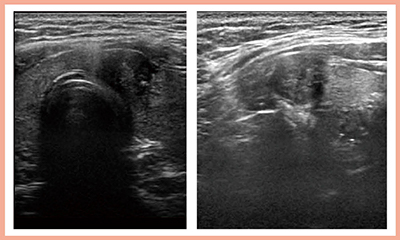

4G CMUTは甲状腺の描出がきわめて良好である。症例1は,甲状腺がんリンパ節転移である。低流速の血流を表示する新しいイメージング技術“Detective Flow Imaging”(DFI)を用いることで,頸動脈の拍動の影響を受けることなく血管走行が描出されており,リンパ節転移も明瞭に診断可能である(図1)。

図1 症例1:甲状腺がんの血管走行およびリンパ節転移の描出